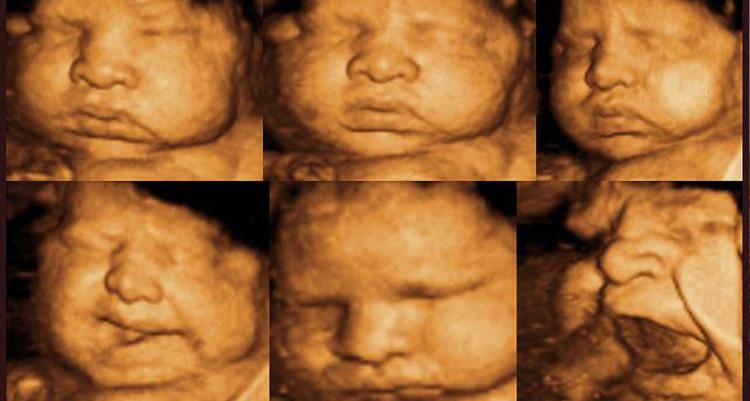

Процедура предназначена для своевременного установления патологий, определения состояния околоплодных вод, стадии развития костной массы, наличия грыж, отклонений в развитии суставов. Можно рассмотреть лицо, руки, пальцы и другие части тела ребенка.

Делают 3Д УЗИ при беременности практически так же, как и обычное ультразвуковое исследование. На ткани организма воздействуют волны ультразвука, отражаются от различных внутренних органов, а затем визуализируются с помощью специального прибора. Но при обычном УЗИ понять, что изображено на экране или распечатке, может только специалист. А вот трехмерное УЗИ лучше для родителей тем, что мать и отец получают объемное изображение, похожее на фотографию, где можно оценить внешность будущего младенца: разглядеть его личико, посчитать, сколько пальцев на руках.

- Диагностика дефектов лица плода, таких как заячья губа.

Трехмерное УЗИ делают на ранних сроках беременности, чтобы лучше оценить состояние плода, удостовериться в том, что его пропорции соответствуют норме, все части тела находятся на своих местах. Визуализация здесь настолько качественная, что возможно разглядеть границы водной оболочки и тела самого эмбриона. При таком подробном изучении достаточно сложно ошибиться при замере различных параметров будущего младенца.

- 3Д изображение позволяет изучать мимику ребенка, что тоже высупает дополнительным показателем наличия или отсутствия каких-либо патологий.

К сожалению, при 3Д-УЗИ далеко не всегда получается идеальное изображение плода: качество визуализации зависит от расположения пуповины, положения плода, количества околоплодных вод и других факторов. Наилучшее изображение при 3Д-УЗИ может быть получено в 20–32 недель, оптимально — в интервале 22–26 недель.

- На изображении, которое получено по результатам исследования, видна мимика будущего младенца. По ней можно судить о том, положительные или отрицательные эмоции он испытывает. Отрицательные эмоции могут говорить о том, что он чувствует боль, это может быть связано с тем, что внутренние органы развиваются неправильно. Если преобладают положительные эмоции, то будущий малыш чувствует себя хорошо и причин для беспокойства нет.